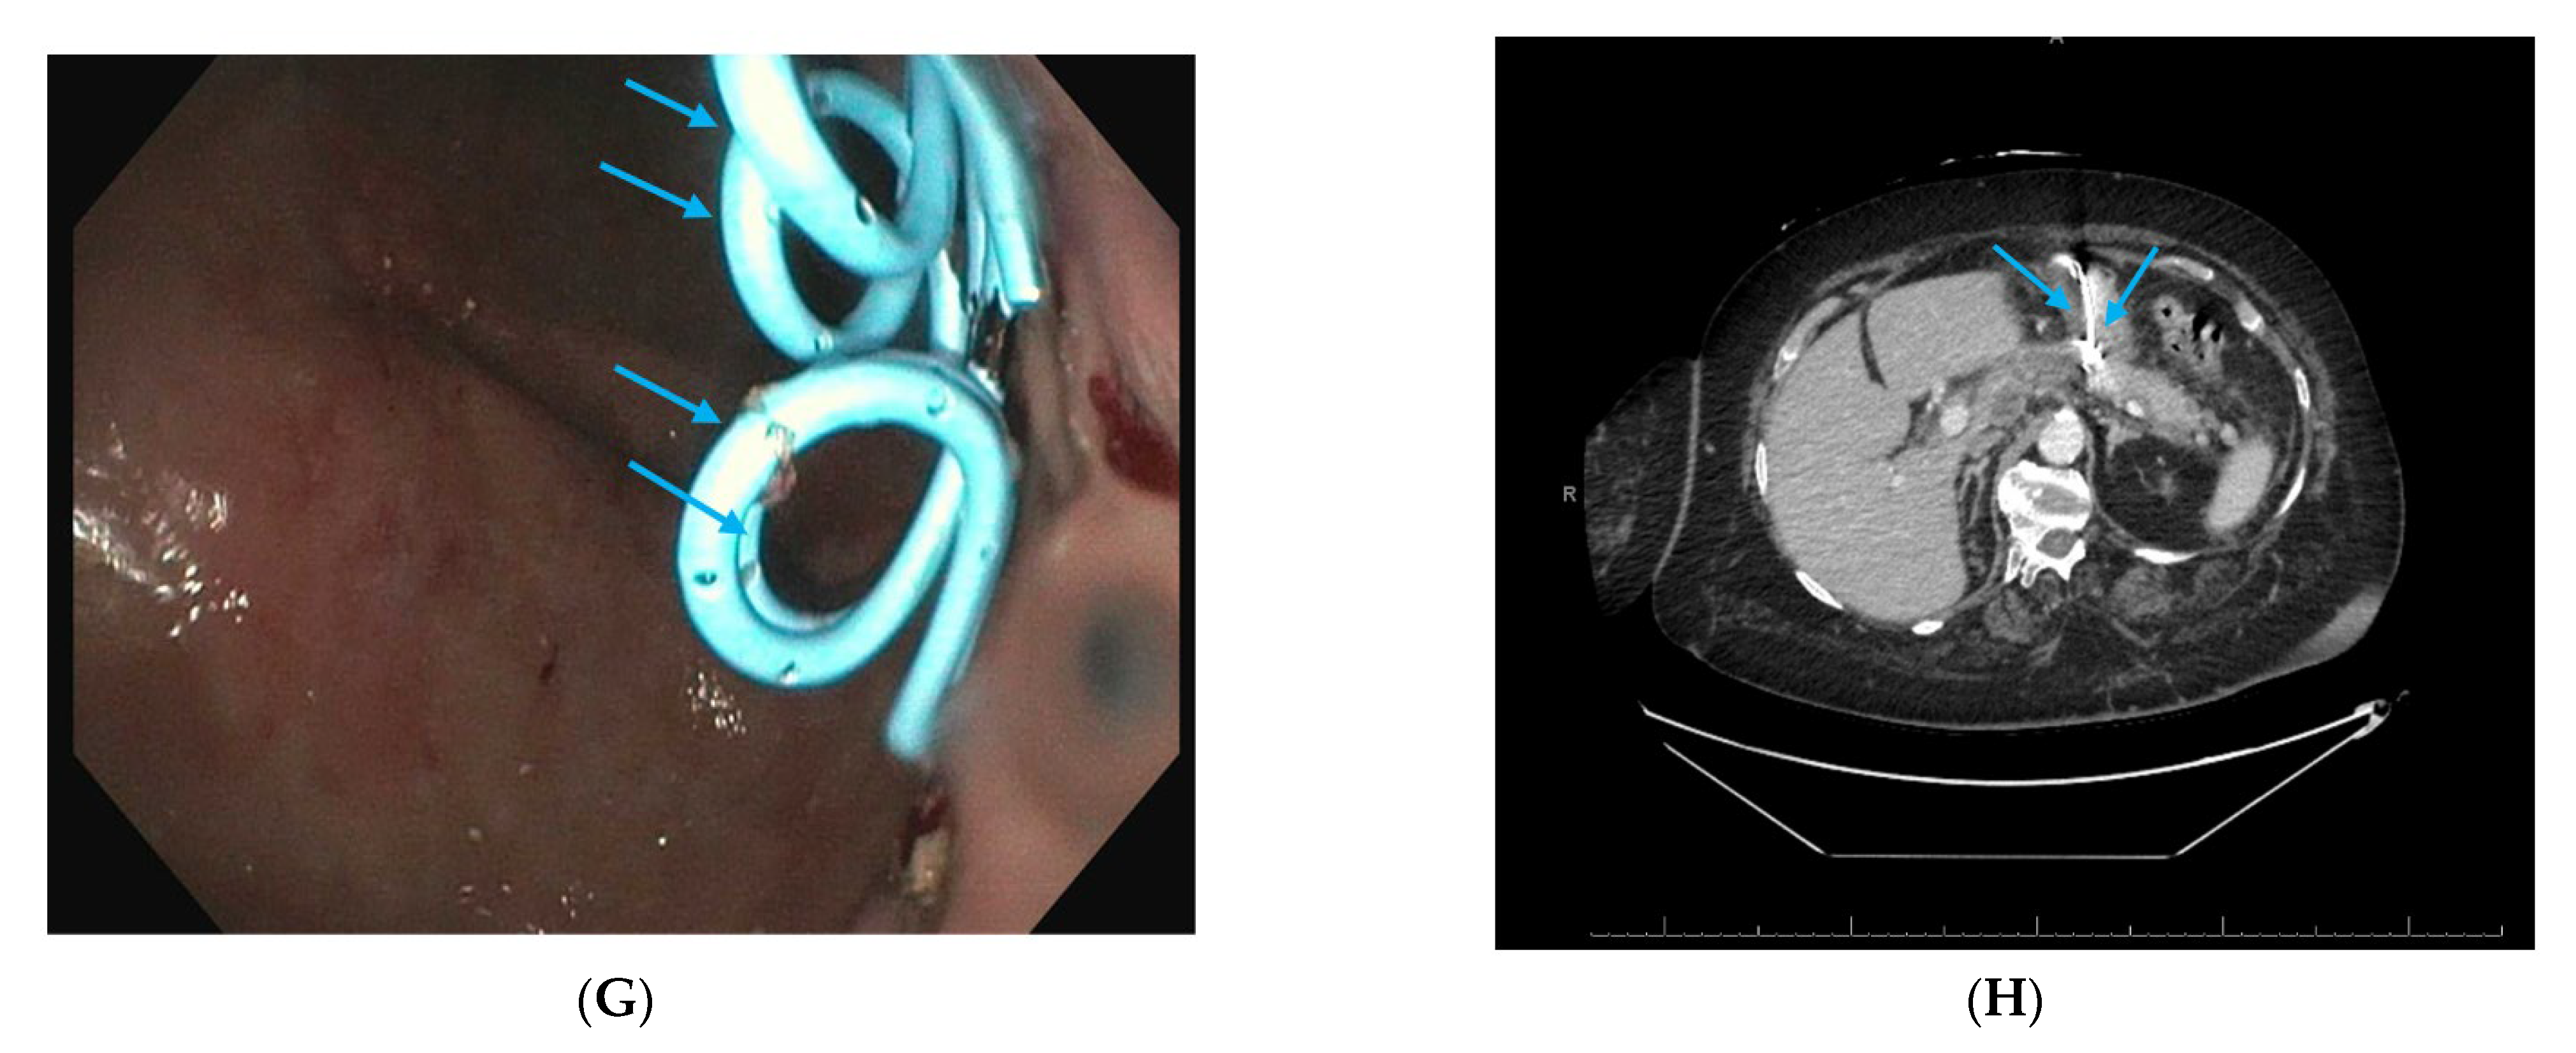

2.5. Direct Endoscopic Necrosectomy

2.6. Dual Modality Drainage

2.7. Interventional Radiology-Guided Embolization of Pseudoaneurysms